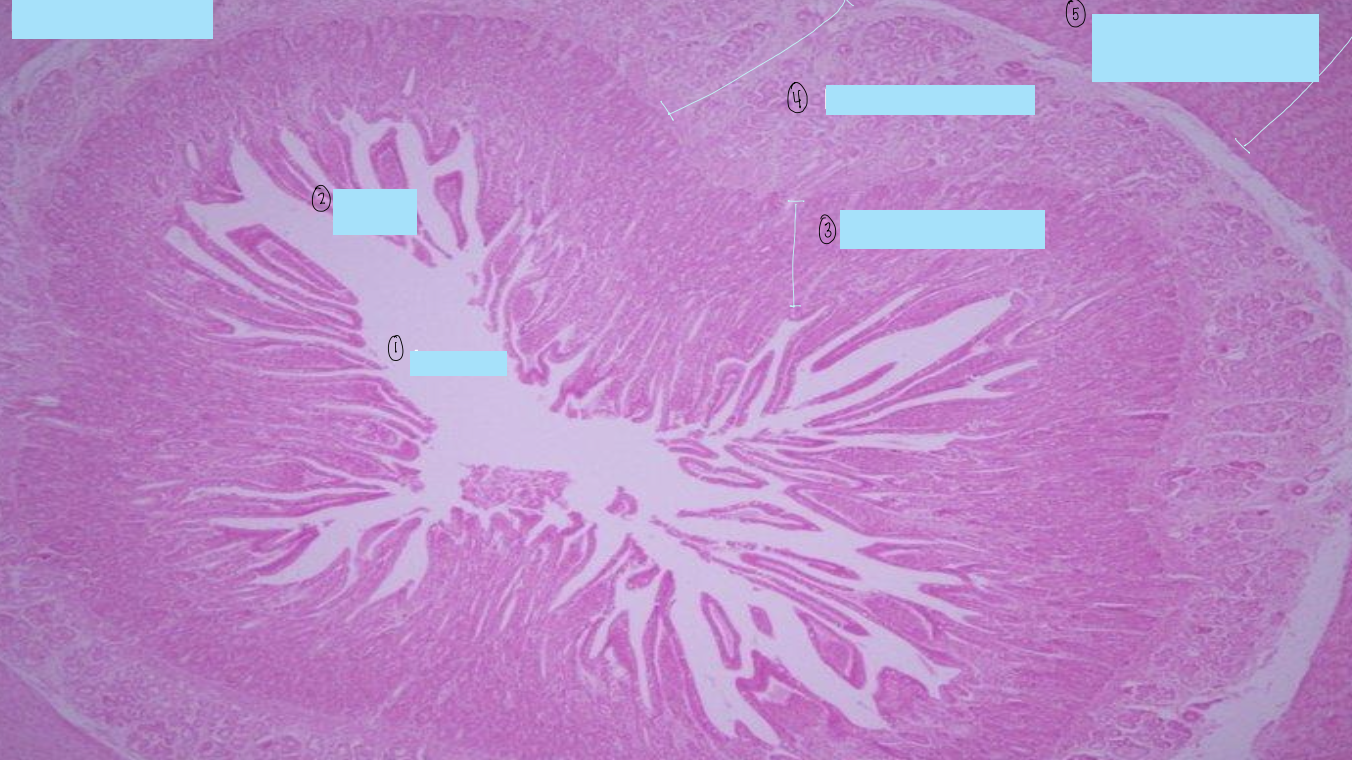

what is this a histological slide of?

duodenum

what is 1?

lumen of duodenum

what is 2?

villi of duodenum

what is 3?

intestinal crypts

what is 4?

brunner’s glands

what is 5?

smooth muscle of tunica muscularis